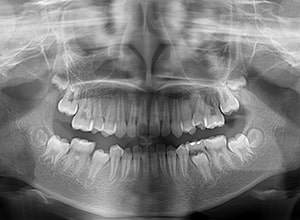

| パノラマ所見 | 右下5は右下6近心傾斜により萌出部位不足が認められた。上下顎8歯胚が確認できた。 |

| 批評・予后 | 右下5及び7の萌出前に右下6を整直させることによって、右下5の自然萌出が可能となり正常咬合への咬合誘導が行えたと思う。 |